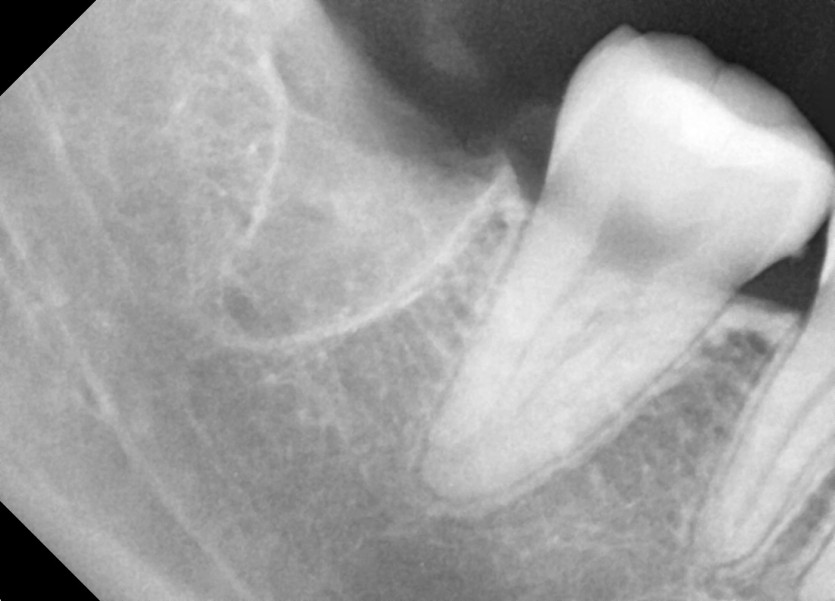

#18,28,38,48 사랑니 발치

구강 외과 전문의가 당일 발치했습니다.